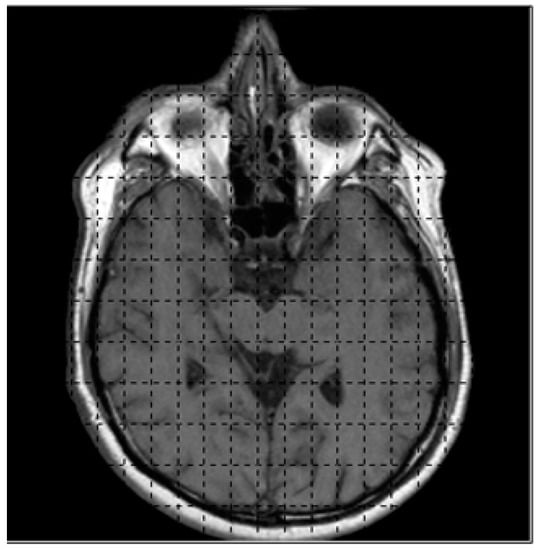

The marching cubes algorithm will generate 3D visualization of 2D binary images by manipulating in form of width x height of image; e.g., in MRI, the resolution is determined by the number of pixels in a specified FOV (Field-of-view), for FOV = 320, the input image with dimension of 320 × 320 will obtain the amount of data = (320 + 1) × (320 + 1) = 103,041; these data will be stored in the array [0, …, 103,040]. The data that will be kept in the array is the intensity value of input image; in the gray-scale image, the range of gray-scale values are varying from 0 to 255 (256 intensity values). The rendering process will be computed starting from the first slide until the last slide of images (k, …, k + 1) as illustrated previously in Figure 4. Figure 8 shows the CT images sequence.

Figure 8.

The CT images sequence used in 3D medical rendering.